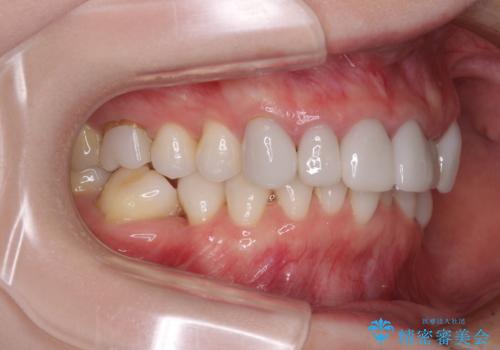

前歯のデコボコと奥歯の咬み合わせをインビザラインで改善

- 上下前歯のデコボコと奥歯の欠損を気にして来院された患者様です。

右下の欠損分は奥歯が倒れ込んでスペースがなくなっていたため、矯正治療により本来の位置に歯を移動させ、オールセラミックブリッジによる欠損補綴治療を行うこととしました。

全顎的にセラミッククラウンが多く装着されているため、インビザラインによる矯正治療を行うこととしました。

右下は移動量が多いため、十分な移動が達成されない場合はワイヤー装置を使用する予定としておりましたが、しっかりとマウスピースを装着してくださったため、前歯とともに十分に歯を動かすことができました。